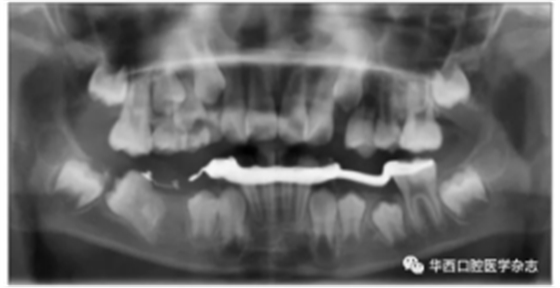

46牙開窗并將舌側扣粘接于近中面。用玻璃離子將鑄造板粘接在下頜,橡皮鏈通過83牙遠中的牽引鉤和46牙上的舌側扣相連,橡皮鏈牽引時對46牙產生一個順時針旋轉的作用力。術中牽引1個月時,見46牙產生順時針旋轉(圖5、6)。治療5個月時,46牙產生明顯的順時針旋轉,基本直立(圖7),由于此時下頜雙側乳尖牙脫落,下頜鑄造板無法固位,于是拆除矯治器,觀察隨診,待后期其余牙齒萌出后行全口固定正畸矯治。

圖 6 治療1個月全景片

圖 7 治療5個月全景片